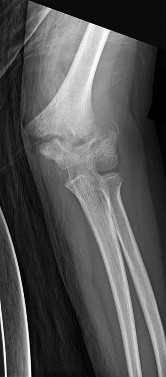

A 5-year-old boy presents with an extension-type Gartland III supracondylar humerus fracture after a fall.

On examination, his hand is well-perfused (pink) with brisk capillary refill, but the radial pulse is absent. What is the most appropriate initial management?

A 7-year-old boy undergoes closed reduction and percutaneous pinning of a displaced supracondylar humerus fracture.

Six hours postoperatively, he is crying uncontrollably on the ward and requires escalating doses of IV opioids. Which of the following is the most reliable early clinical indicator of compartment syndrome in this pediatric patient?

A 6-year-old boy sustains a completely displaced, extension-type supracondylar humerus fracture (Gartland Type III). Upon presentation, his hand is pale and pulseless. Following closed reduction and percutaneous pinning in the operating room, the hand becomes warm and pink with a capillary refill of 2 seconds, but the radial pulse remains unpalpable. What is the most appropriate next step in management?

Explanation

A 6-year-old boy falls from monkey bars and sustains a widely displaced posterolateral Gartland type III supracondylar humerus fracture. Which of the following neurologic deficits is most likely to be observed on physical examination?

Question 64

A 6-year-old boy sustains a severe extension-type supracondylar humerus fracture. On examination, the hand is pink and warm with normal capillary refill, but the radial pulse is not palpable.

What is the most appropriate initial management?

Question 73

A 7-year-old boy sustains a completely displaced extension-type supracondylar humerus fracture. On neurological examination, he is unable to flex the interphalangeal joint of the thumb and the distal interphalangeal joint of the index finger. Which nerve is injured?